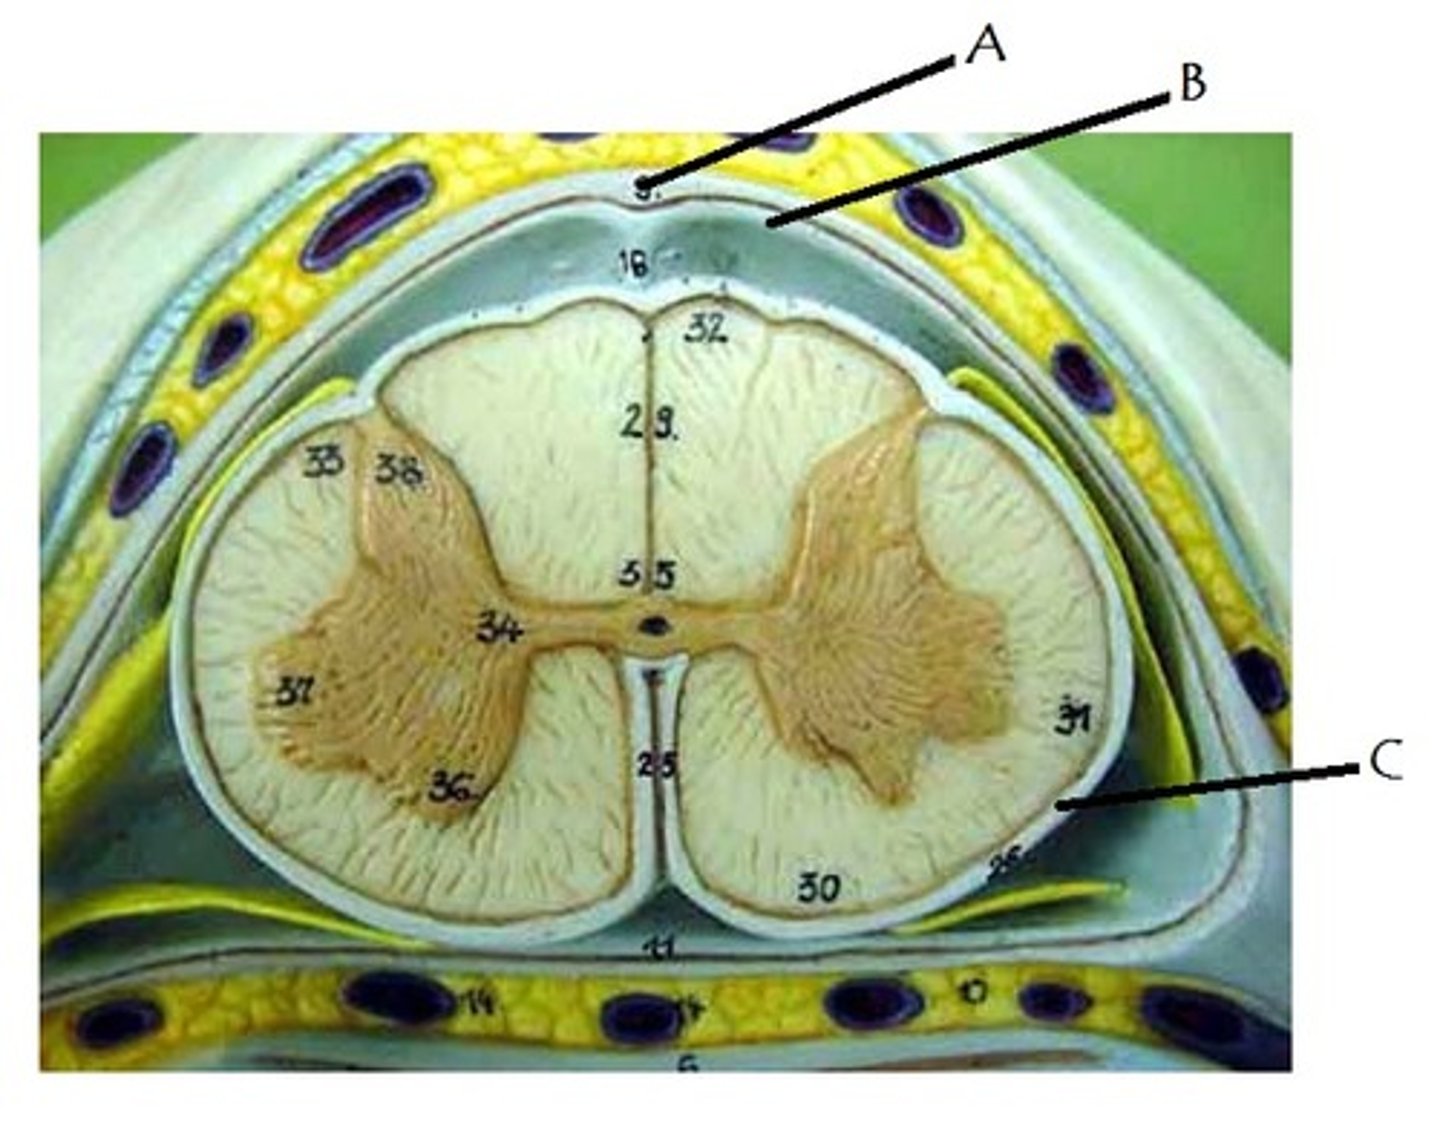

posterior white column

A

anterior white column

C

lateral white column

B

posterior gray horn

anterior gray horn

lateral gray horn

gray commissure

central canal

arachnoid mater

B on model

subarachnoid space

pia mater

denticulate ligaments